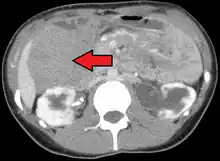

Morfología

Los tumores desmoides se tratan de masas mal delimitadas, firmes, de color gris-blando, con un tamaño entre 1 y 15 cm en su diámetro máximo. Son elásticas y duras, y producen una infiltración considerable del músculo, el nervio y la grasa circundantes.

El patrón histológico característico consiste en fibroblastos con características citológicas benignas organizados en fascículos anchos unidos entre colágeno denso.[4]